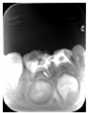

65MO深大龋洞,色棕黄,质软,叩痛(+),不松动,牙龈红肿,未见瘘管。 X线片示:冠部低密度影达髓腔,根分歧区大面积低密度影,近远中根内侧壁见吸收。25牙胚存,未拍全。 64MO深大龋洞,色棕黄,质软,叩痛(+),不松动,牙龈略红肿。 X线片示:根分歧区密度减低。 84OD深大龋洞,色棕黄,质软,叩痛(-),不松动, 85MO牙色充填体周围见龋坏,色黑,质软,叩痛(±),不松动,龈无异常。 X线片示:根周见低密度影,44,45牙胚存,未拍全。 54DOL深大龋洞,色黑,质软,叩痛(-),不松动, 55O窝沟色黑,卡探针,叩痛(-),不松动,龈无异常。 74OD,75MO半年前曾于外院行充填治疗,现检查见充填体边缘色黑,卡探针,充填体略有松动。

乳牙根管治疗术是治疗乳牙根尖周病的有效方法,通过根管预备和药物毒去除感染物质对根尖周组织的不良刺激,并用可吸收的充填材料充填根管,促进根尖周病愈合。 在第一恒磨牙未完全萌出之前,为防止乳牙早失造成第一恒磨牙近中移位,对于第二乳磨牙的较大面积根尖周病变我们采取保守治疗,根管治疗后需定期复查,一旦发生病变扩大及时拔除,在此病例中第一恒磨牙未完全萌出,我们对65,85进行试保留,半年后临床检查无异常,x线片显示病变较初诊时缩小,建议继续观察。